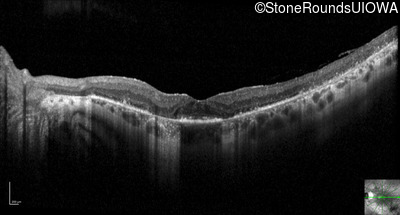

Optical Coherence Tomography - Left - 20/25 sc

Exemplar / OCT Stack

OCT Stack